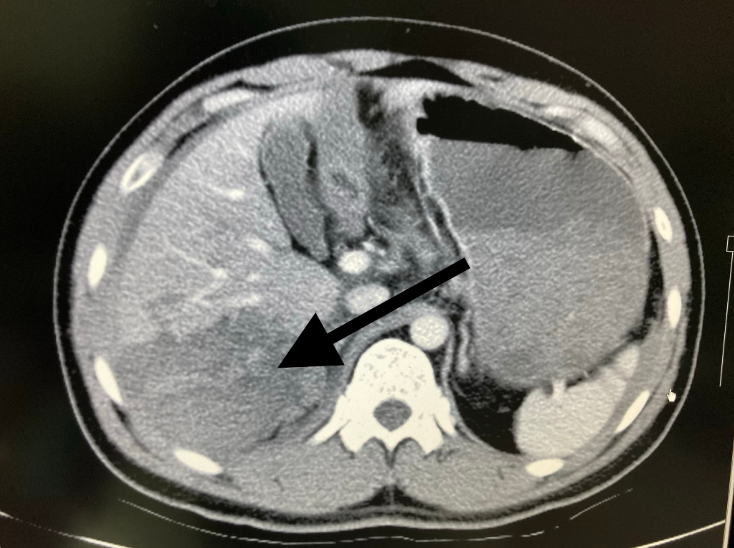

2014年病人,右胸腹撞击伤,术前ct显示肝破裂(右半肝密度不均)